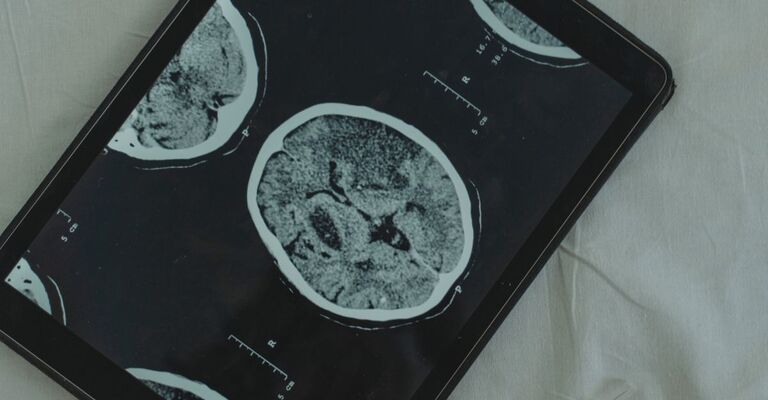

dottoressa di spalle controlla una radiografia

Tubercolosi, l’Oms indica una nuova strategia: cosa cambia nella lotta alla malattia

L’Oms presenta una nuova roadmap per migliorare la lotta alla tubercolosi: un approccio strutturato per definire le priorità, ottimizzare le risorse e sostenere i Paesi nella pianificazione di interventi mirati.